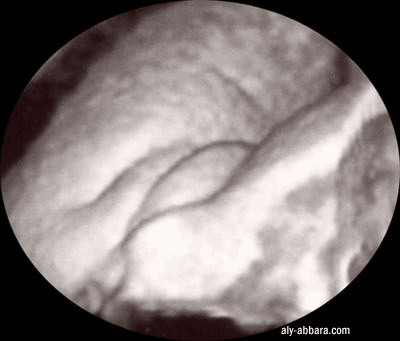

Organes génitaux externes féminins chez un fœtus de 32 SA

Échographie 3D (trois dimensions)